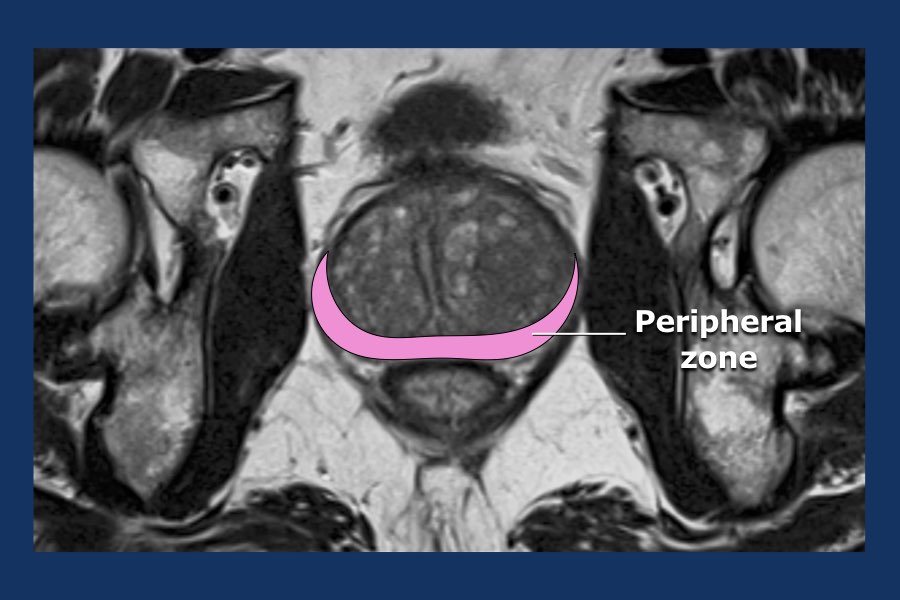

The Radiology Assistant Prostate Anatomy Radiology Assistant Mri Prostate Prostate mri has become an increasingly frequent examination faced in daily radiological practice and is usually acquired as. See videos and images of normal and abnormal prostatic. Radiology department of the haaglanden mc, alrijne hospital and erasmus mc, the netherlands mri of the prostate has become increasingly popular. Radiology Assistant Mri Prostate.